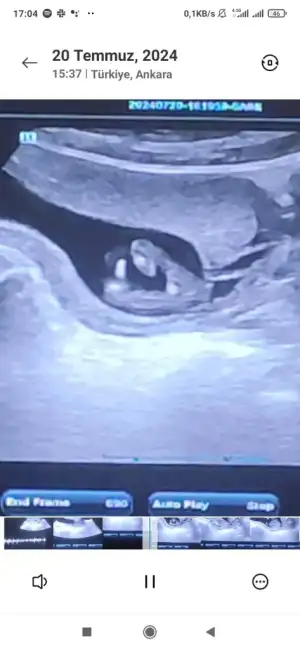

13+3 uz doktor kız dedi ama ben cinsiyette emin olamadım anlayan kızlar yardımcı olabilir misiniz ? Bebişimin bacak arası fotograflari

Kız cnm bebek bacak arası cok net aradaki beyazlık pipi olabilir gibi seni yanıltmasın erkeklerde direk ortada cıkıntı şeklınde belli oluyor